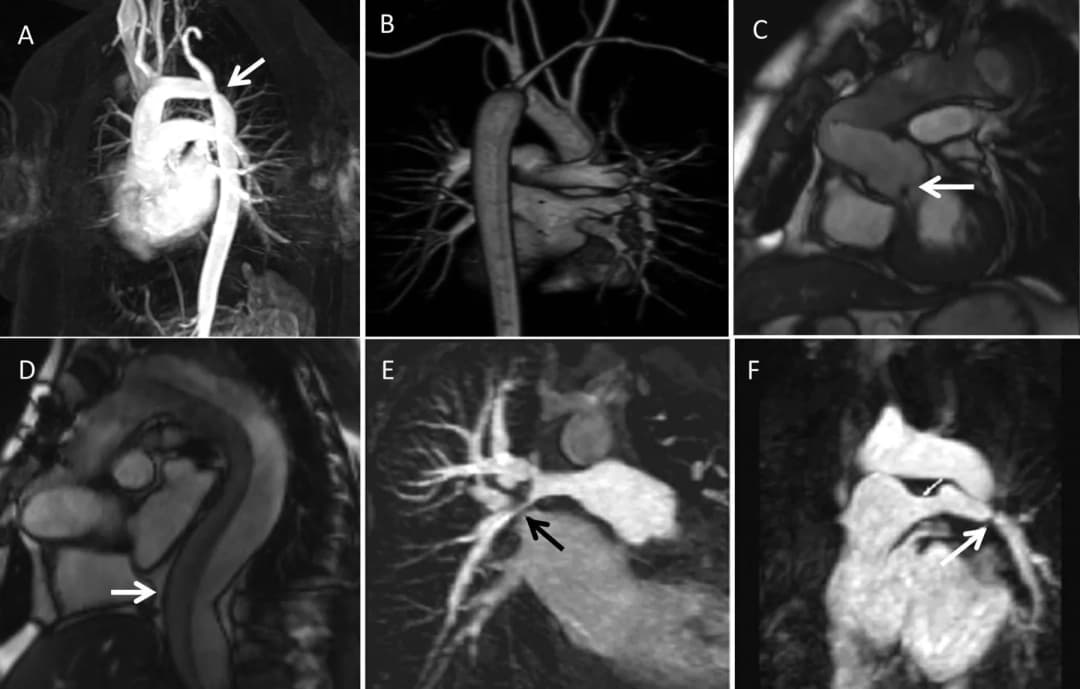

suy timsiêu âm timbệnh timChẩn đoán suy timchụp cộng hưởng từ tim

Ứng dụng của cộng hưởng từ tim mạch trong chẩn đoán suy tim

Suy tim là một tình trạng ảnh hưởng đến khả năng bơm máu của tim. Chẩn đoán sớm rất quan trọng, và chụp cộng hưởng từ ti...